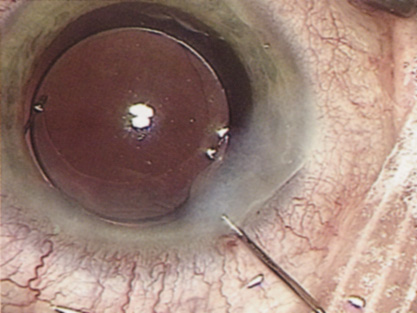

INTRAOCULAR LENS IMPLANTATION

At the turn of the century, the incidence of posterior capsular opacification (PCO), the most common untoward event after surgery, was plummeting as the result of a square edge design on the IOL optic. The haptics themselves had evolved from Prolene material to polymethylmethacrylate and then Alcon introduced a soft haptic on a single-piece acrylic platform. Every company developed an injector for improved IOL insertion, and industry was teaming up with innovative surgeons in developing a number of optic modifications. Attempts to achieve multifocality with diffractive optics had been introduced by 3M and their design team of Richard Lindstrom, John Sheets, and Robert Osher. This technology was placed on the back burner until Allergan developed the array multifocal IOL. Alcon purchased and improved the 3M defractive optic and introduced ReStor IOL on a single-piece acrylic platform. The surgical assault on presbyopia accelerated as Eyeonics developed the Crystalens, the first IOL with a pliable optic aimed at generating accommodation, a concept introduced a decade before by Spencer Thornton.33 A toric optic was developed by Staar Surgical; Pharmacia introduced Tecnis, the first spherical aberration-correcting IOL; and Alcon developed the first blue-light–filtering optic to provide macular protection. The once narrowly defined specialty of cataract and IOL surgery was exploding with new ideas and technologies. Smaller-incision IOLs were being designed that could be injected through <2-mm incisions. A host of surgeons, including Amar Agarwal, Jorge Alio, Richard Packard, Hiroshi Tsuneoka, Virgilio Centurion, Howard Fine, and Randy Olson, were exploring microincisional cataract surgery through 1.5-mm incisions by separating the sleeveless ultrasound tip from the irrigating chopper.

Refractive lens replacement and phakic implantation also were gradually earning a rightful place in anterior segment surgery. In the early 1980s, Franco Verzella from Italy initially removed the clear lens for extreme myopia, but surgeons were concerned about the incidence of retinal detachment in this group of high-risk eyes. Robert Osher performed the first clear lensectomy for hyperopia in 1985 and although the risk of retinal detachment was lower, these eyes were challenging both in surgery and in accurately selecting the IOL.34,35 John Gayton's novel approach of using “piggyback” IOLs met with enthusiasm until interlenticular opacification emerged.36 AcriTec engineers from Germany identified a method of manufacturing lens power up to +60 diopters. Phakic implantation with IOLs fixated in the anterior chamber (Baikoff, Kelman, Choyce) and the posterior chamber (Fyodorov, Adatomed, PRL, Staar Surgical) were being developed. The iris-supported Verisyse (Artisan developed by Jan Worst) became the first phakic IOL approved in the United States.